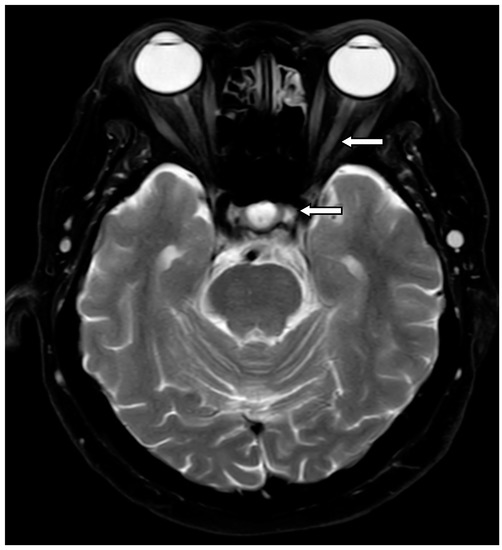

| Segmental enhancement of AVP—no. (%) | ||||||||

| Orbital optic nerve | 40 (52.6) | 15 (37.5) | 17 (70.8) | 8 (66.7) | 0.02 | 0.01 | 0.073 | 0.544 |

| Intracanalicular optic nerve | 10 (13.2) | 2 (5.0) | 4 (16.7) | 4 (33.3) | 0.032 | 0.135 | 0.021 | 0.236 |

| Intracranial optic nerve | 6 (7.9) | 1 (2.5) | 0 (0) | 1 (8.3) | 0.126 | 0.061 | 0.412 | 0.451 |

| Optic chiasm | 0 (0) | 0 (0) | 0 (0) | 0 (0) | - | - | - | - |

| Optic tract | 0 (0) | 0 (0) | 0 (0) | 0 (0) | - | - | - | - |

| ≥2 consecutive segments | 10 (13.2) | 2 (5.0) | 4 (16.7) | 4 (33.3) | 0.032 | 0.135 | 0.021 | 0.236 |